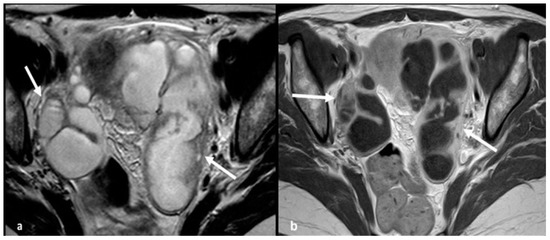

2.1.1. High-Grade Serous Cystadenocarcinoma (HGSC)

2.1.2. Serous Borderline Neoplasms and Low-Grade Serous Cystadenocarcinoma